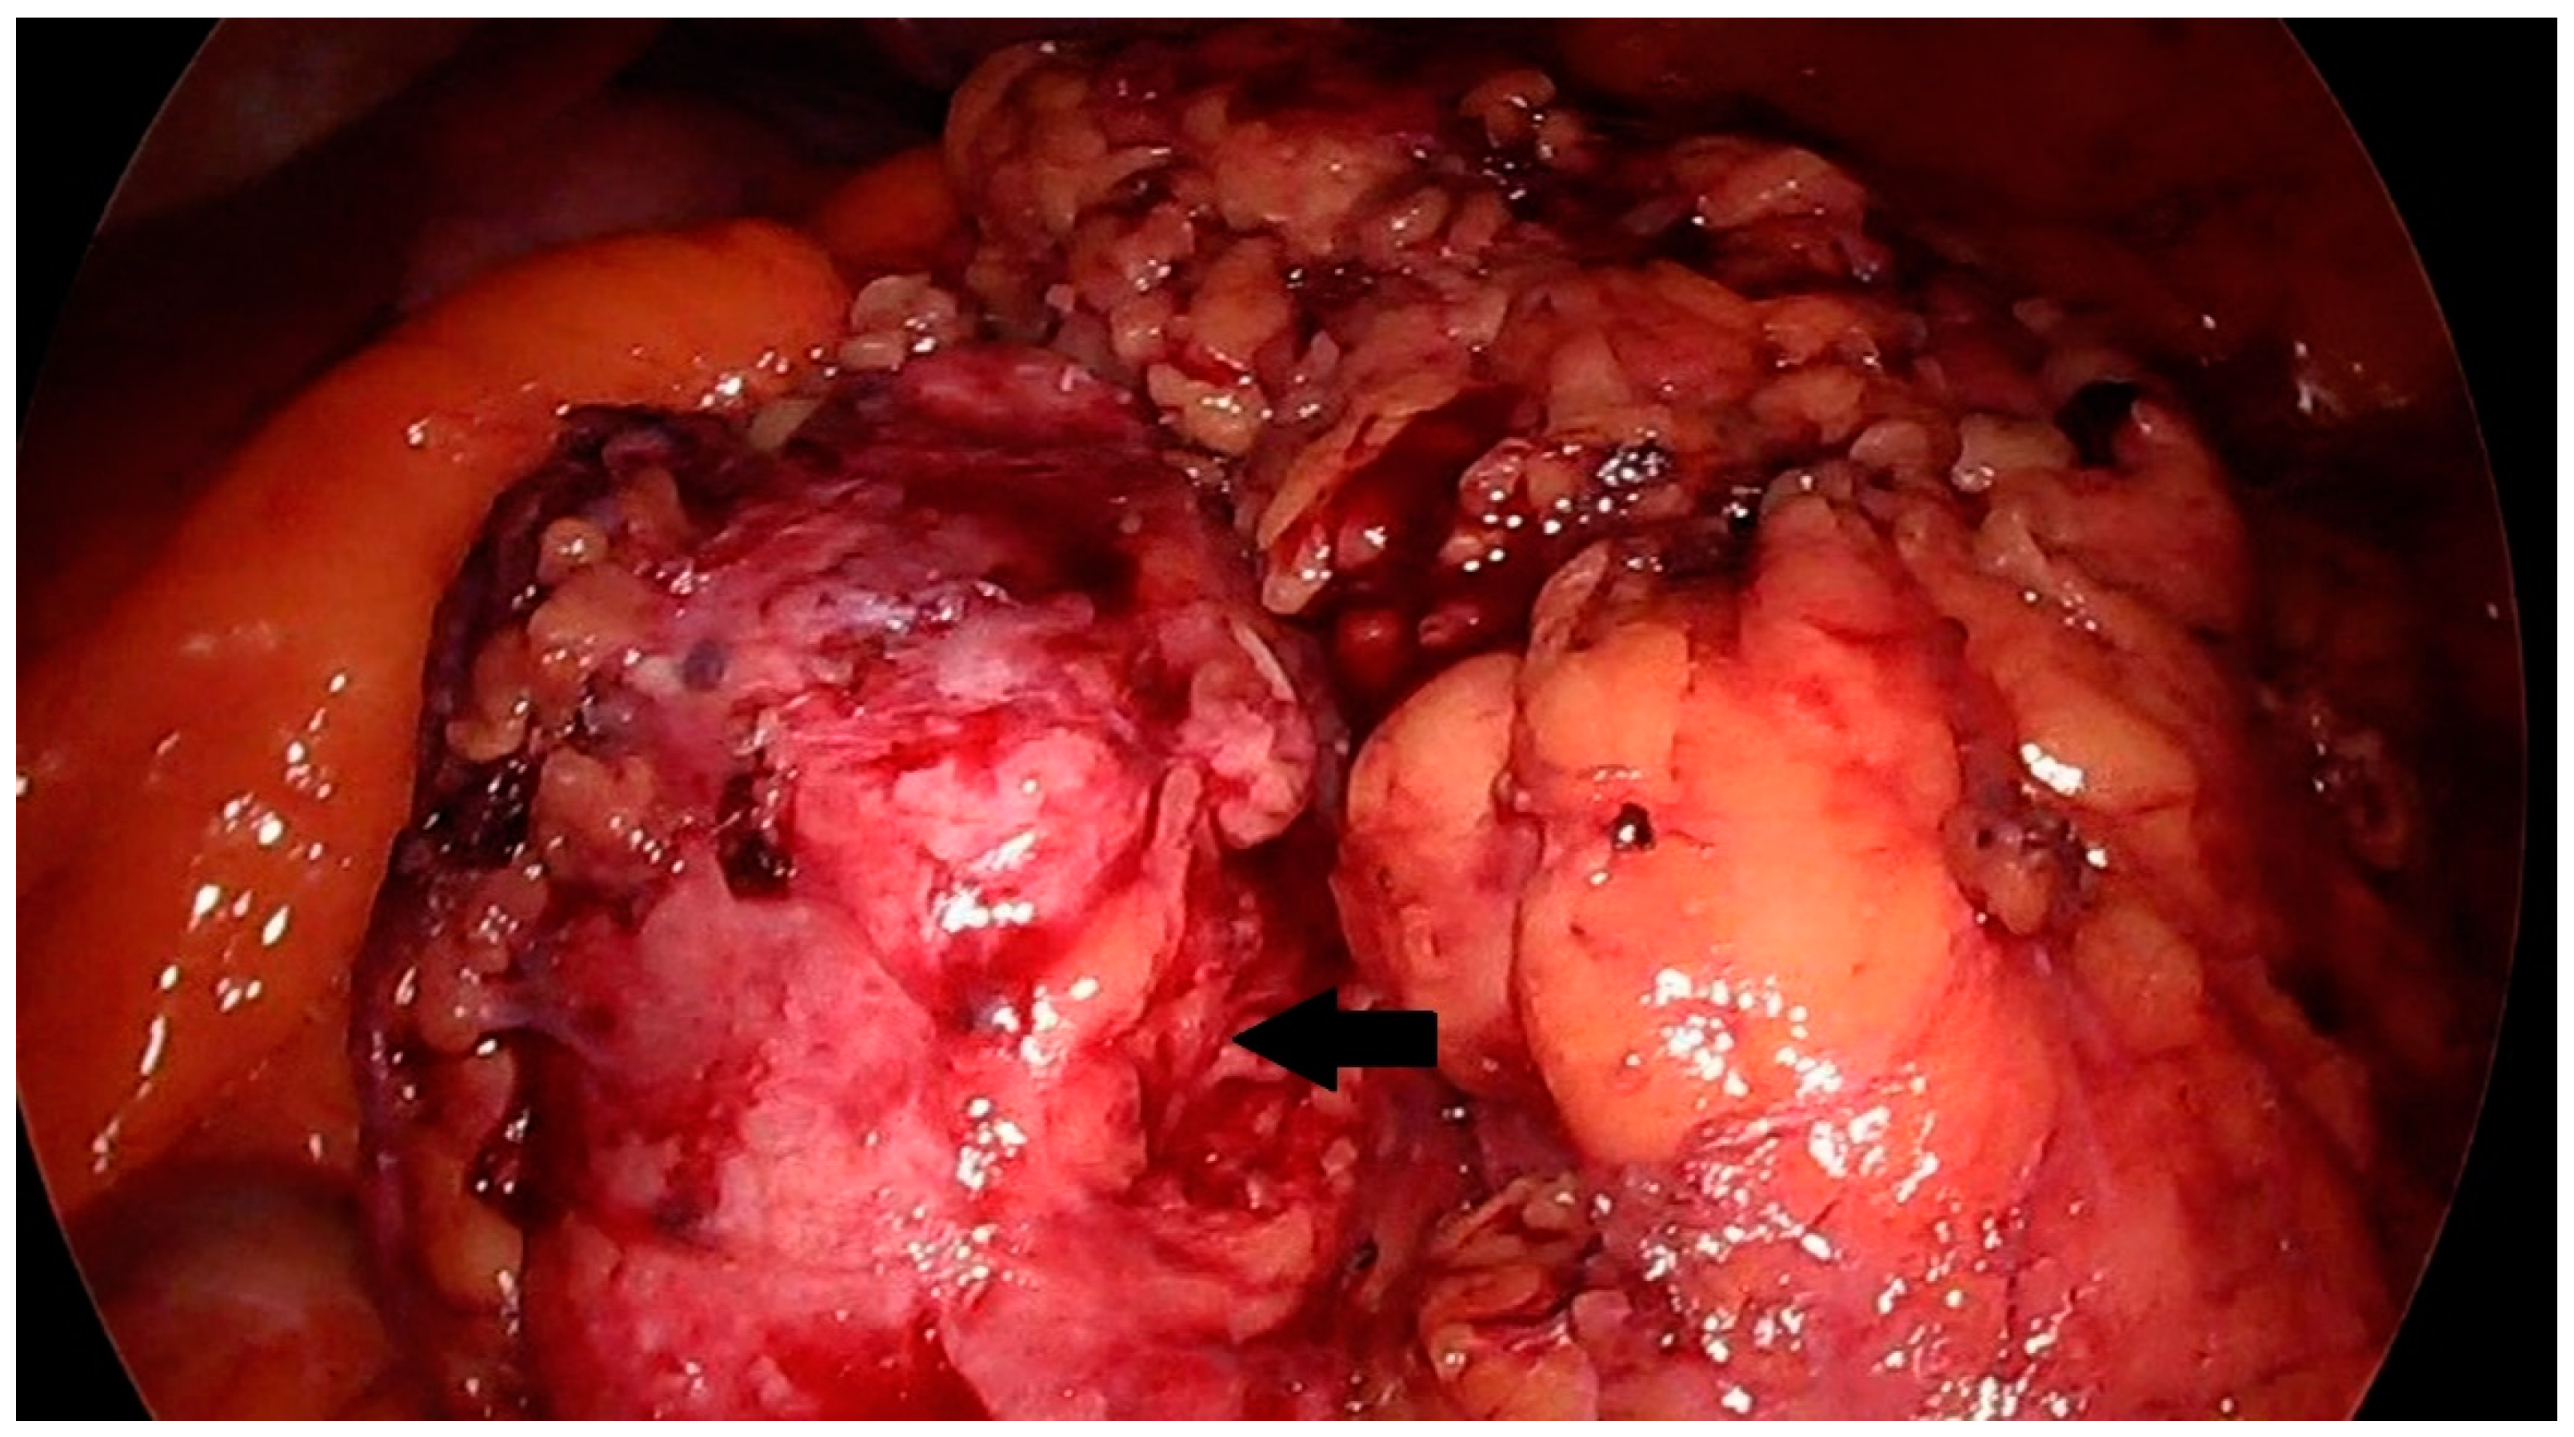

Other examinations showed no abnormalities in the patient. No pathological lesions were observed in the lungs. No pathologically changed lymph nodes were visualized. Because of the typical clinical presentation, the patient was qualified for laparoscopic renal tumor removal with preservation or complete removal of the kidney, depending on the intraoperative findings. Intraoperatively, a tumor was visualized that was not directly related to the kidney. It was located near the renal hilum and was closely related to the renal vessels. The lesion could be removed radically with a minimally invasive technique during laparoscopic evaluation. The location of the tumor made resection with a margin of healthy tissue impossible. Achieving a resection margin would require removal of the kidney. The lesion was completely dissected macroscopically from the renal vessels and surrounding tissues with preservation of the capsule (Figure 2 and Figure 3).

Figure 2.

Solid mass in the region of the left kidney, intraoperative image. The prepared lesion is marked with an arrow.